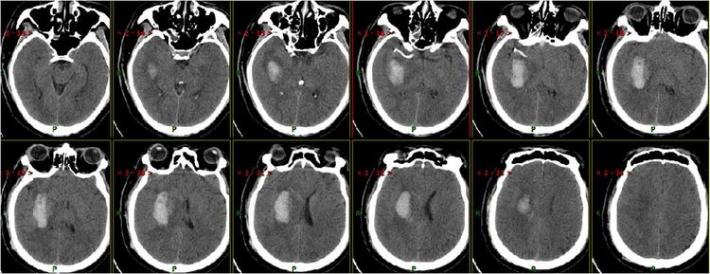

患者术后1天,左侧肢体肌力0级,NIHSS评分:12分,复查头部CT:右侧基底节区出血,范围约22mmX49mm,请脑外科会诊:做好立体定向穿刺准备,注意观察患者病情变化,密集复查头部CT。

术后3天复查头部CT

术后7天复查头部CT

术后15天复查头部CT

术后21天复查头部CT